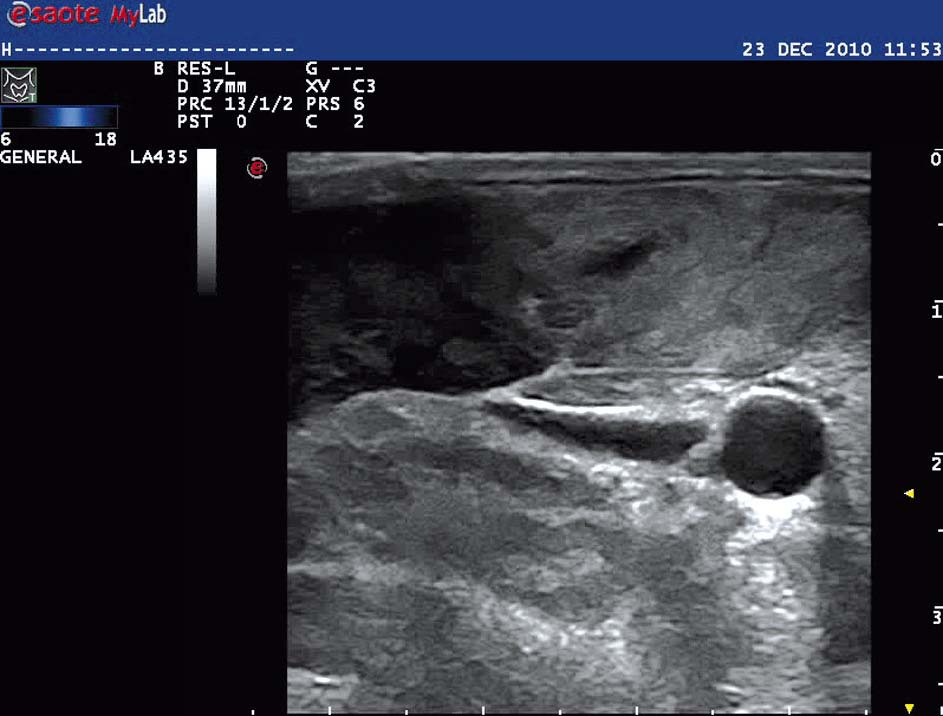

Manifestacja ultrasonograficzna zajętych mięśni szkieletowych w przebiegu ciężkiej postaci zapalenia skórno-mięśniowego z rabdomiolizą

Zapalenie skórno-mięśniowe (dermatomyositis – DM) to przewlekła, idiopatyczna miopatia zapalna przebiegająca ze zmianami skórnymi. Do charakterystycznych objawów choroby należą osłabienie siły mięśniowej obręczy barkowej i/lub biodrowej oraz występowanie typowych zmian skórnych.